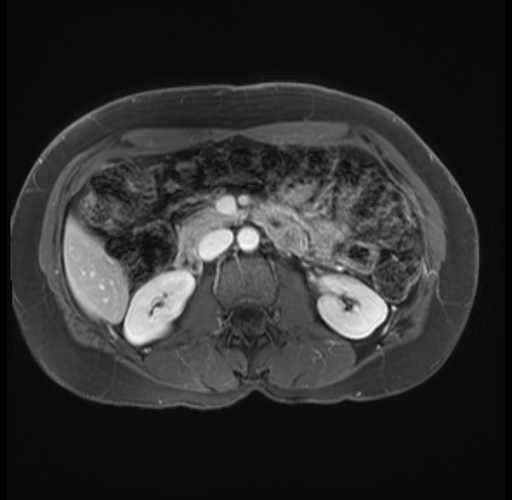

Imaging Analysis

Look through the patient's CT scan to identify any areas of concern for the necessary procedure.

Based on your CT findings, which issue(s) are present and would give reason for "planned slowing down moment(s)" in this case?

Considering a standard distal pancreatectomy procedure, what step(s) of the operation would you do differently in this case?